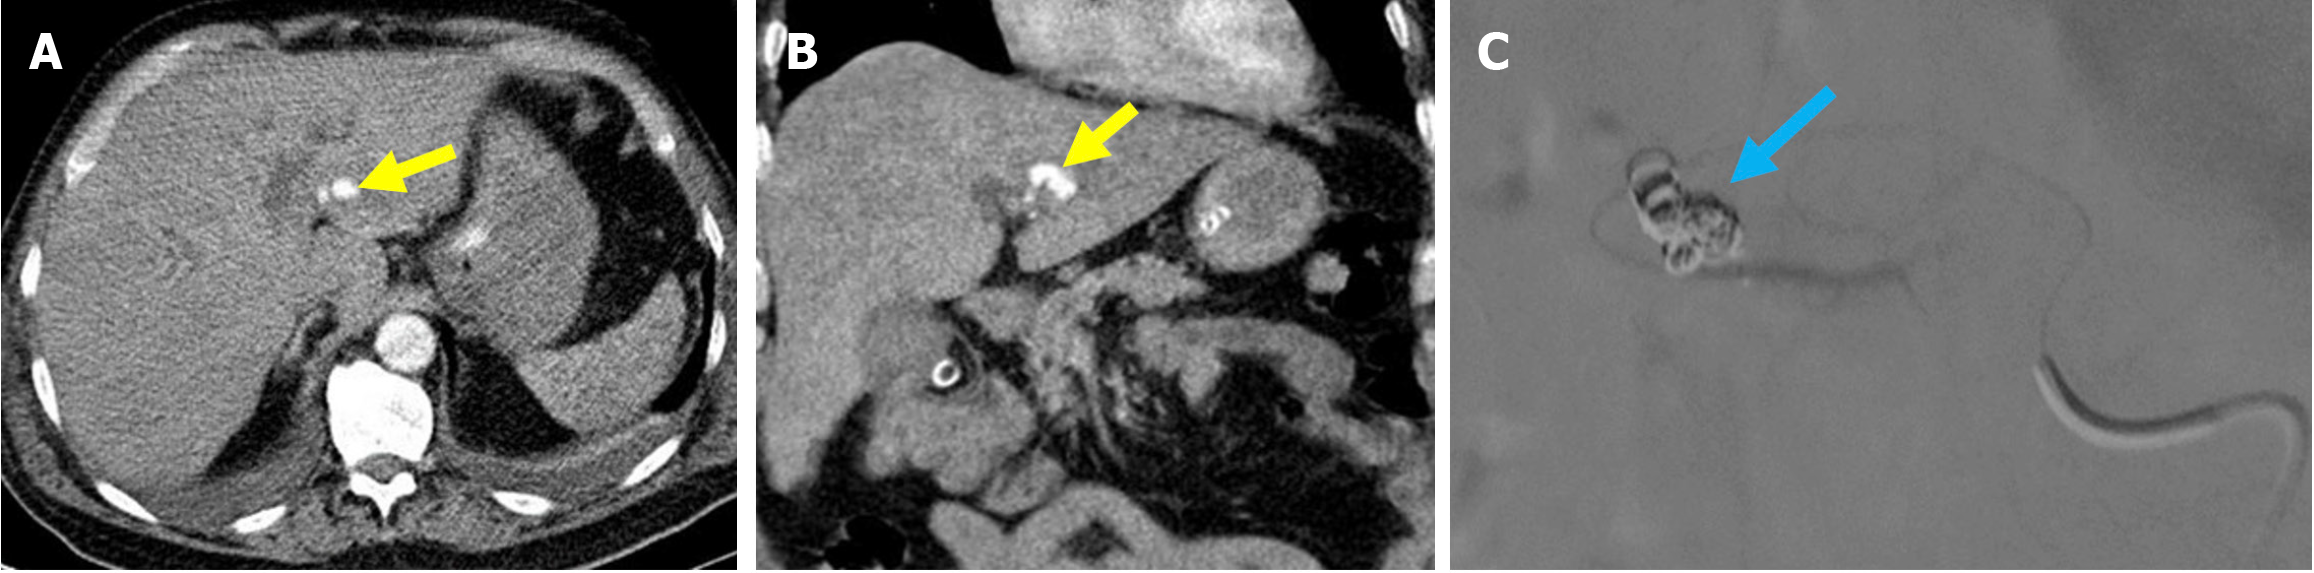

Certain imaging findings normally appear after ERCP and should not be mistaken for pathological conditions. In particular, the air within the intraextrahepatic bile ducts, which is consistent with pneumobilia, can be observed. This finding may continue for several weeks to several months in patients who have undergone sphincterotomy. Contrast material injected during ERCP may also appear on CT imaging as characteristic layering within the bile ducts and gallbladder (Figure 1)[9,13].

Figure 1 Typical imaging findings of air and contrast material in the biliary system after endoscopic retrograde cholangiopancreatography. A and B: Coronal (A) and axial (B) noncontrast computed tomography images showed normal post-intervention findings in a 70-year-old female patient. The patient underwent endoscopic retrograde cholangiopancreatography for choledocholithiasis. Despite having normal post-procedural laboratory values, she presented with abdominal pain and mild guarding upon physical examination. Air was present within the intrahepatic bile ducts and gallbladder (orange arrow). Contrast material used during the endoscopic retrograde cholangiopancreatography was visualized as layering within the intrahepatic bile ducts (blue arrow) and the gallbladder (yellow arrow).